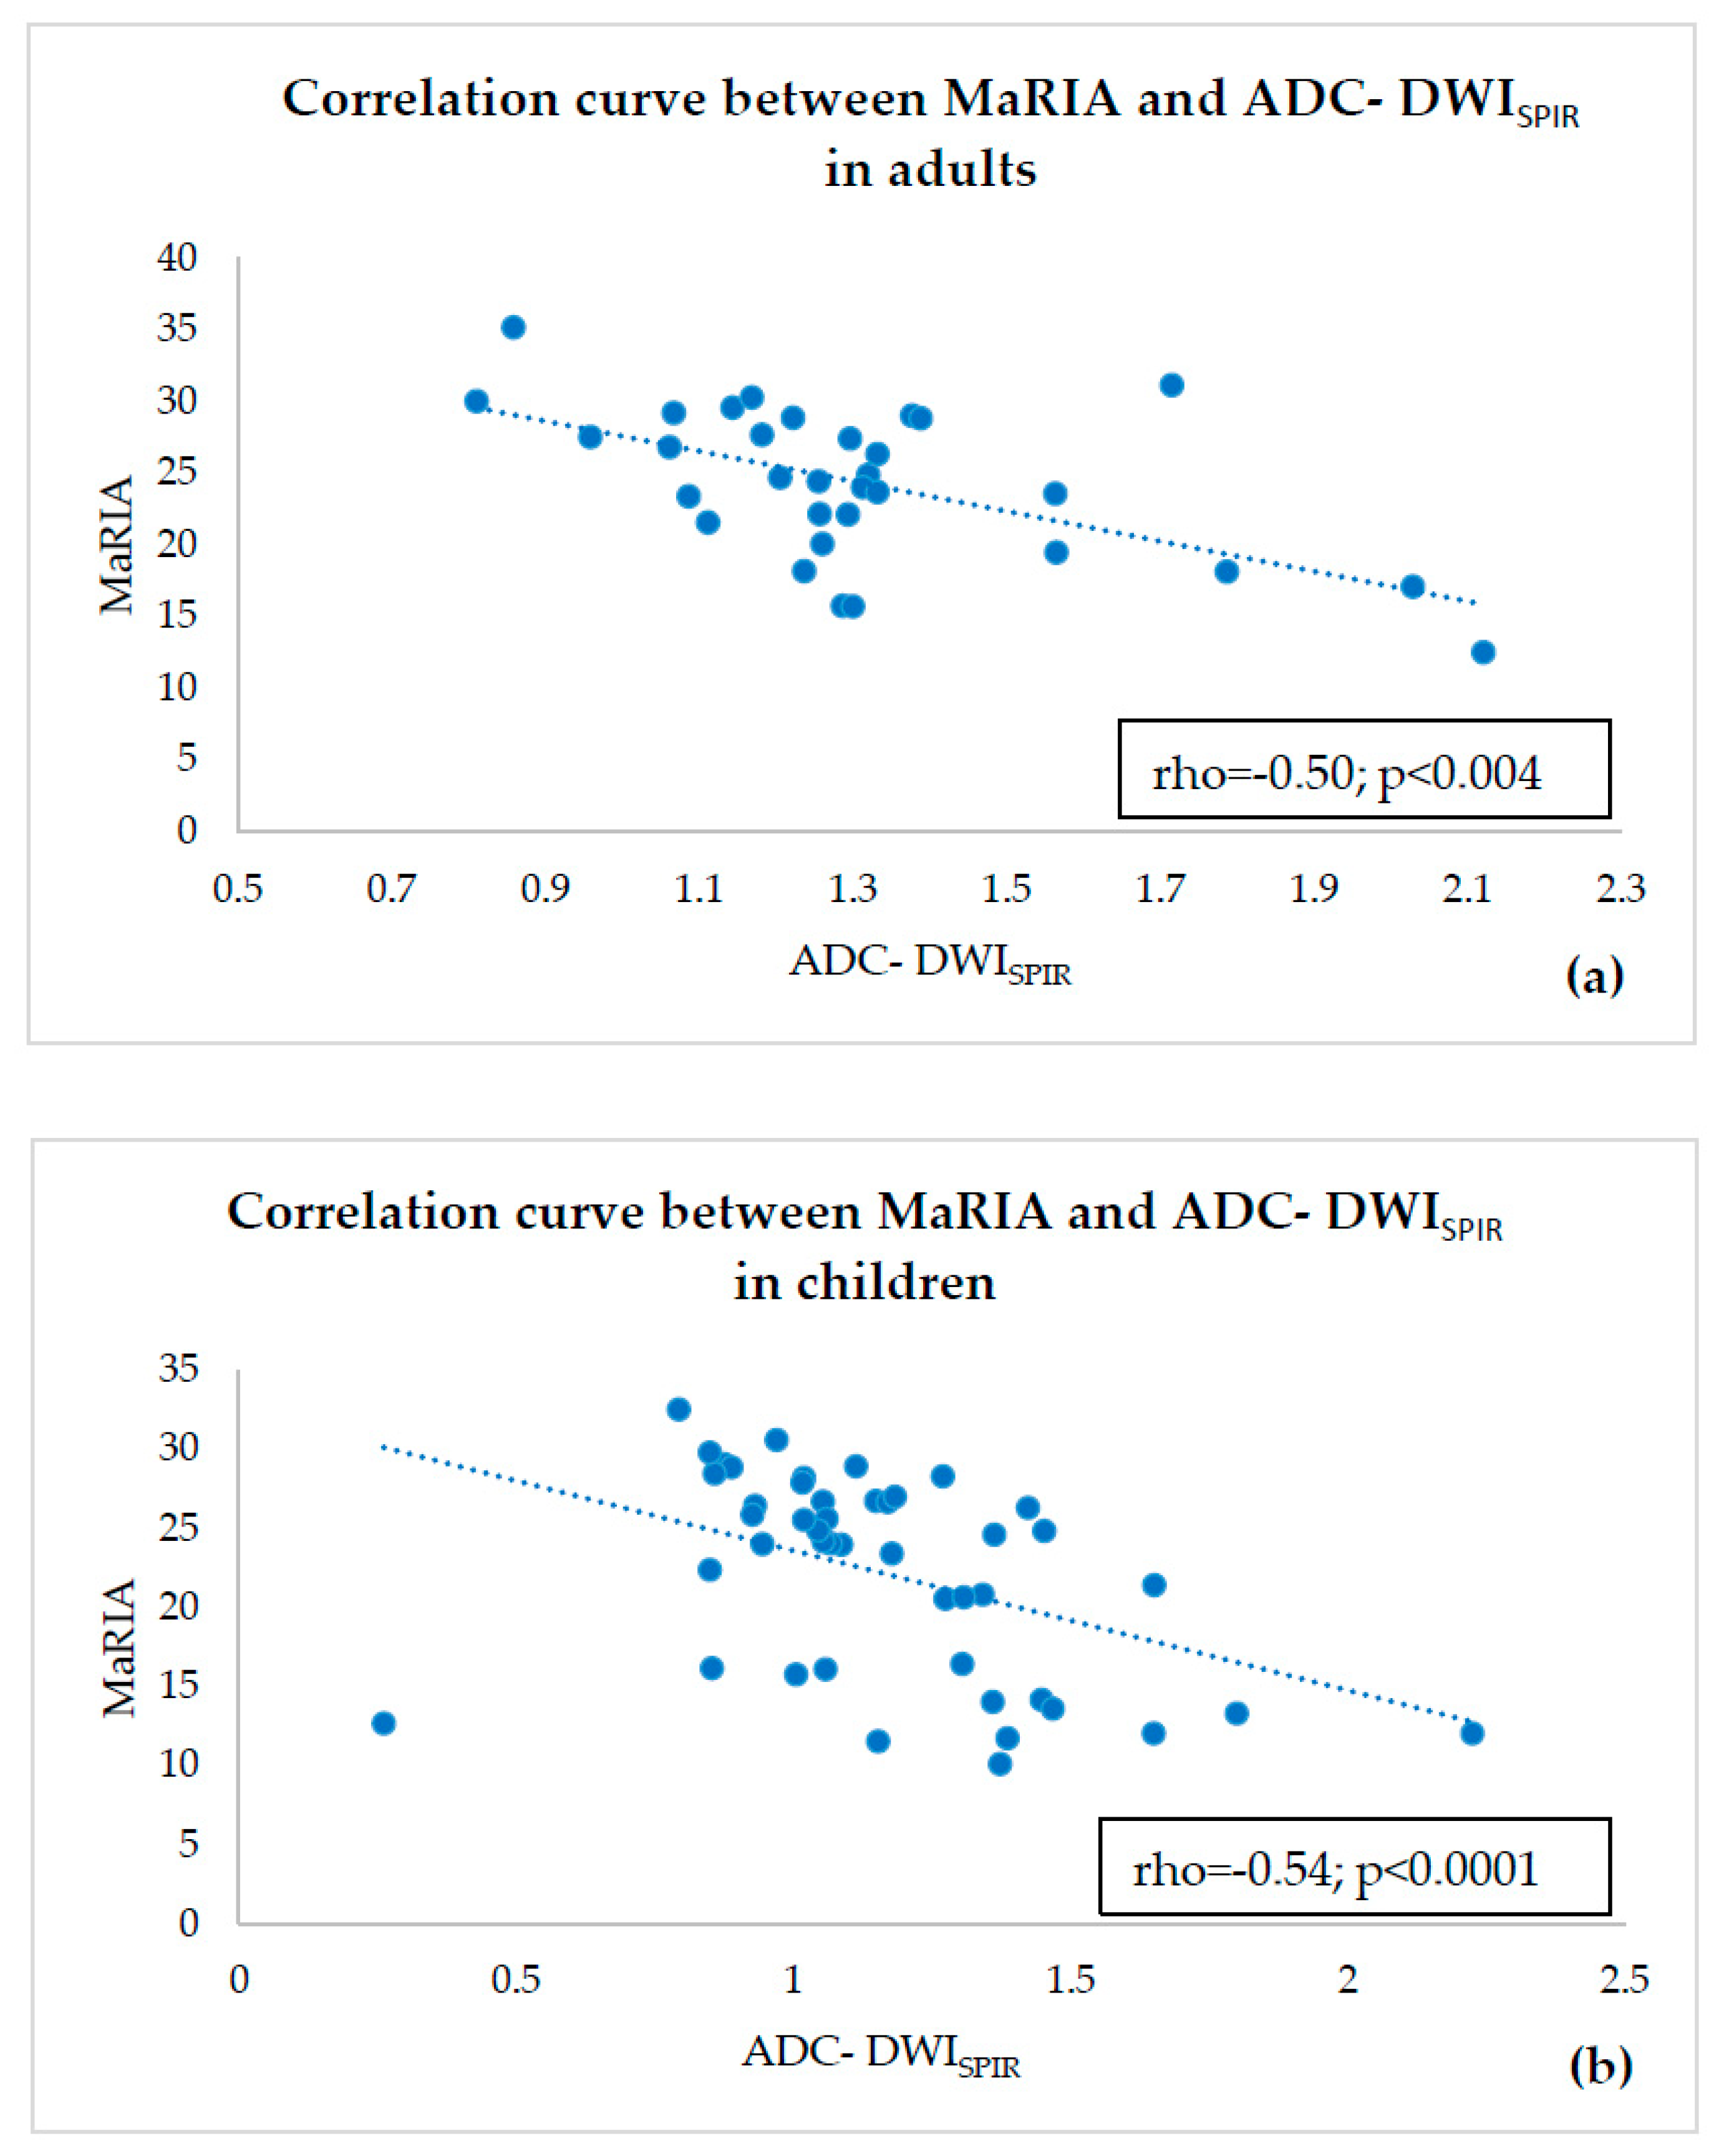

- estimating correlations of ADC-DWISPIR and ADC-DWISTIR values with the corresponding MaRIA, calculated from the contrast–enhanced sequences within the same bowel segments,

- ADC values of both adults and children were compared within a single fat suppression technique, and we observed statistically significant ADC-DWISPIR difference between adults and children (1.31 × 10−3 mm2/s, SD 0.29, vs. 1.16 × 10−3 mm2/s, SD 0.31; p = 0.02), with 12.12% lower ADC values in children compared to adults, but no statistically significant difference between the ADC-DWISTIR values in adults and children (1.09 × 10−3 mm2/s, SD 0.49, vs. 1.20 mm2/s × 10−3, SD 0.44; p = 0.38);

- both DWISPIR and DWISTIR techniques were compared within one patient group, both in adults and children. In this case, the analysis showed difference of 16.73% between ADC-DWISPIR and ADC-DWISTIR values in adults, being lower in DWISTIR (1.31 × 10−3 mm2/s, SD 0.29, vs. 1.09 × 10−3 mm2/s, SD 0.49; p = 0.03), but did not show difference between ADC-DWISPIR and ADC-DWISTIR values in the children’s group (1.16 mm2/s × 10−3, SD 0.31, vs. 1.20 × 10−3 mm2/s, SD 0.44, p = 0.97).